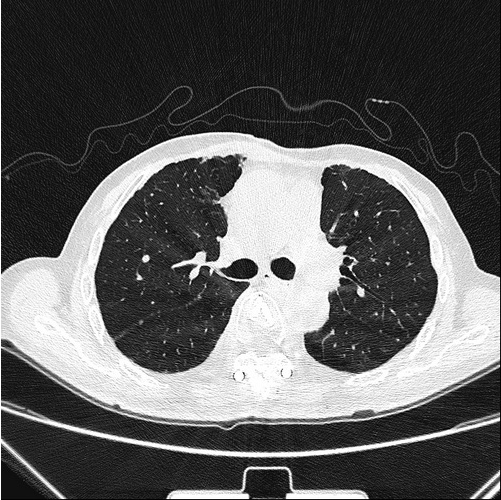

後因新冠疫情,病患無法再北上接受放射碘治療,由陳華宗醫師幫他申請健保給付的標靶藥物 (lenvatinib),使用兩個月後,肺部電腦斷層檢查顯示米粒狀轉移病灶已全消失。後續胸椎磁振造影追蹤也顯示胸椎骨溶及後壓現象明顯改善。陳華宗醫師提到,經數年治療,至今未發現肺部有再犯現象。標靶藥物治療過程期間病患曾出現高血壓、腹泄、體重減輕等藥物副作用,經調整藥量以上症狀也獲改善。

右圖:經標靶治療後,電腦斷層顯示肺部轉移病灶已完全消失。(陳華宗醫師提供)